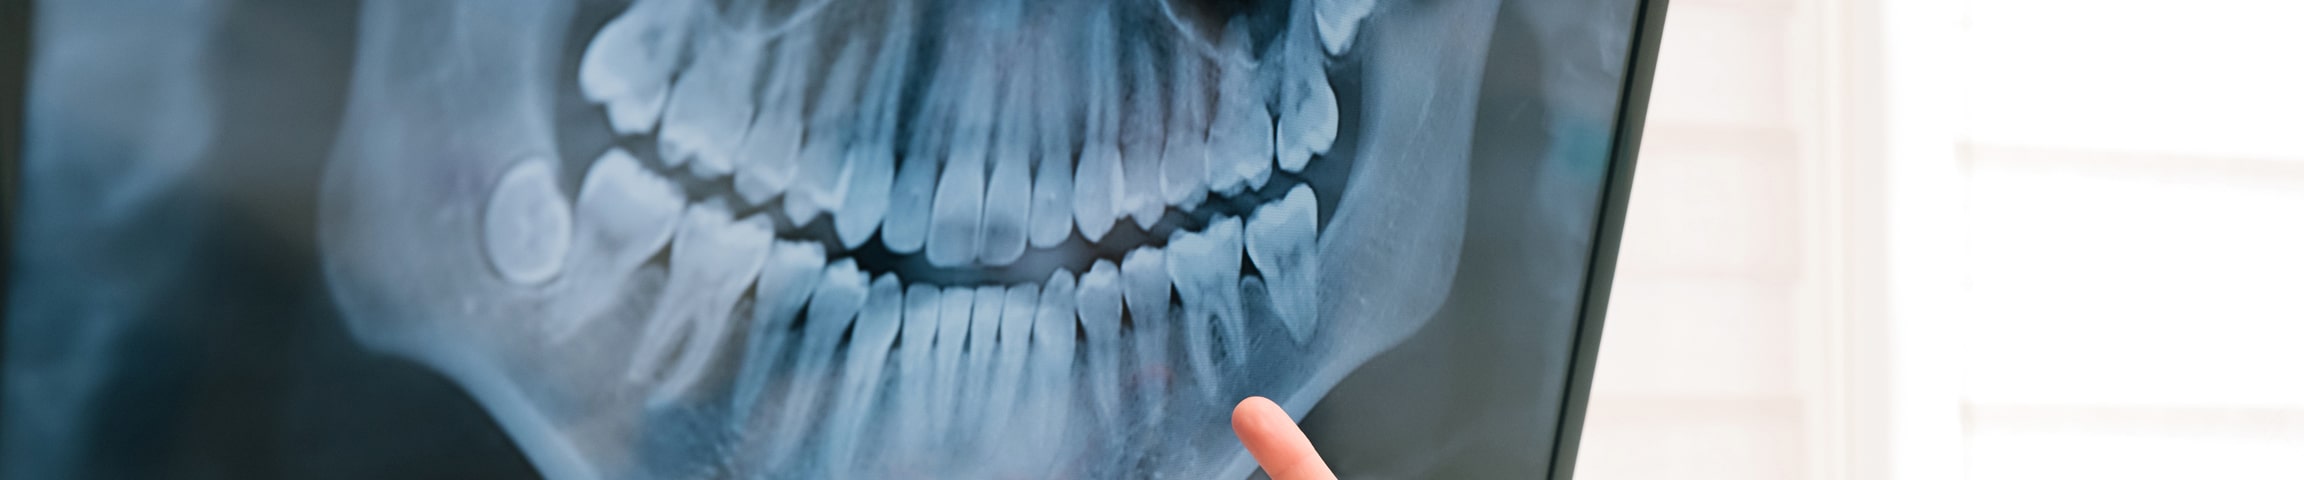

Your dentist diagnoses TMJ problems after discussing your symptoms and medical history. They examine your jaw joint and its range of motion and often recommend X-rays, a CT scan, or an MRI to find the underlying cause of TMJ discomfort.